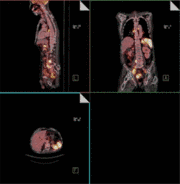

Beispiel 2: Lymphom: Staging mit FDG PET/CT (genaue Erfassung des Ausmaßes der Erkrankung vor Therapiebeginn)